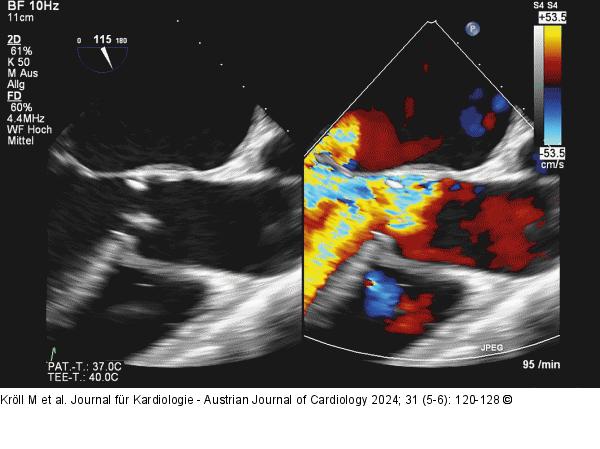

Abbildung 7: Echo Biplanes TEE mit und ohne Farbdoppler, akute AI bei entzündlich destruierter Klappe. |

Biplanes TEE mit und ohne Farbdoppler, akute AI bei entzündlich destruierter Klappe. |